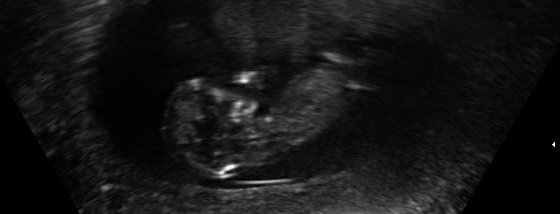

I was 11w5d when I had the scan, although I was measuring 12w1d. I know it's still pretty early, but am wondering if you see anything on these (terrible quality) scan pics! Attachment 23572Attachment 23571Attachment 23573Attachment 23574Attachment 23575